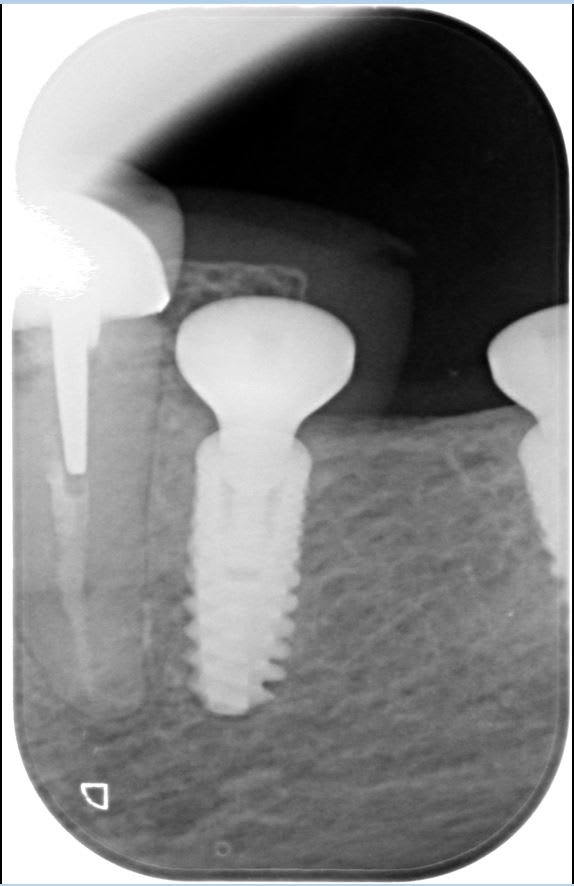

Je dois réaliser la prothèse sur ces 2 implants qui ont été posés en Mai 2024 dans un centre dentaire qui a fermé depuis.

Cliniquement, tout me semble ok mais je ne sais pas identifier la marque de ces implants.

Global D In-Kone

J'ai contacté Global D pour commander les analogues et transferts mais ils veulent savoir si c'est du Twin Kon, du in Kone ST ou du in Kone WD.

Comment faire pour savoir quelle gamme c'est ?

Inkone universal.. st